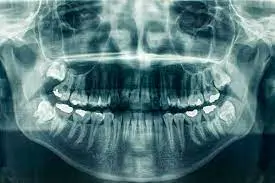

Panoramic X-Rays: A Comprehensive View of Oral Health

A key advancement within digital X-ray is the panoramic X-ray, which captures a broad view of the entire mouth, including the teeth, jawbone, and surrounding structures. This type of imaging provides valuable information that can guide treatments for various dental concerns, such as:

- Impacted teeth (e.g., wisdom teeth)

- Jaw disorders (e.g., TMJ)

- Oral cancers

- Bone abnormalities

Panoramic X-ray are particularly helpful for planning complex procedures, such as dental implants or orthodontic treatment, as they provide a complete view of the patient’s oral anatomy.